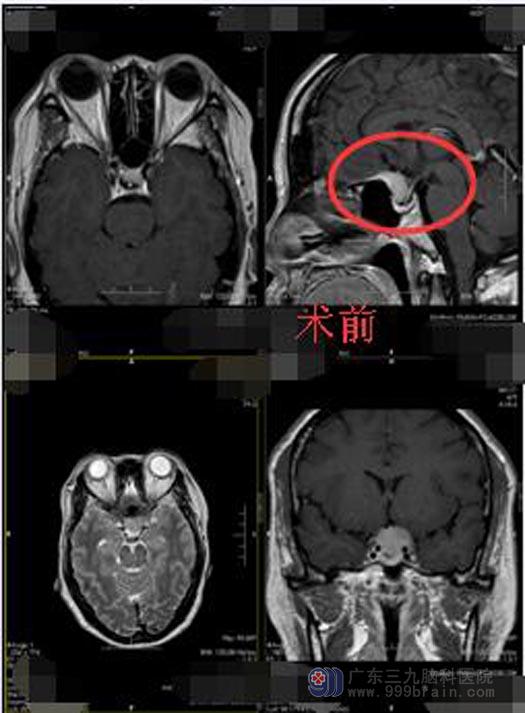

慌了神的左女士为进一步确认病情,在家人陪同下来到了广东三九脑科医院。在神经外五科,初步诊断为鞍结节占位,影像检查显示:鞍结节一异常信号影,大小约1.0cm×1.5cm×1.9cm,邻近脑膜显示脑膜尾征,双侧视神经鞘膜受累,以左侧为著,因左侧视神经颅内段受压变细,视交叉轻度受压。

手术切除是治疗鞍结节脑膜瘤最有效的治疗方法,直径小于3cm小型肿瘤较易全切除,可获得治愈的良好效果。左女士及家属同意手术方案。手术中,分离前纵裂蛛网膜及部分导静脉,在蝶骨区可见灰白色肿瘤组织,肿瘤起源于鞍膈,质一般,血供比较丰富,手术主刀鲁明副院长在显微镜下将肿瘤分块切除,双侧视神经与颅内动脉保护良好,垂体体柄位于后部,肿瘤全切,创面止血,术中出血量少,术程顺利。